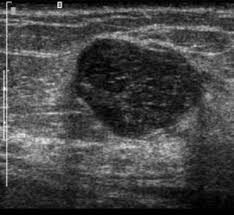

الورم الغدي الليفي في الثدي ويب طب

الورم الليفي في الثدي ما هو الأعراض العلاج التشخيص أنواع الأورام الليفية

الأعراض في ورم غدي ليفي الثدي وأنواعه وأسبابه